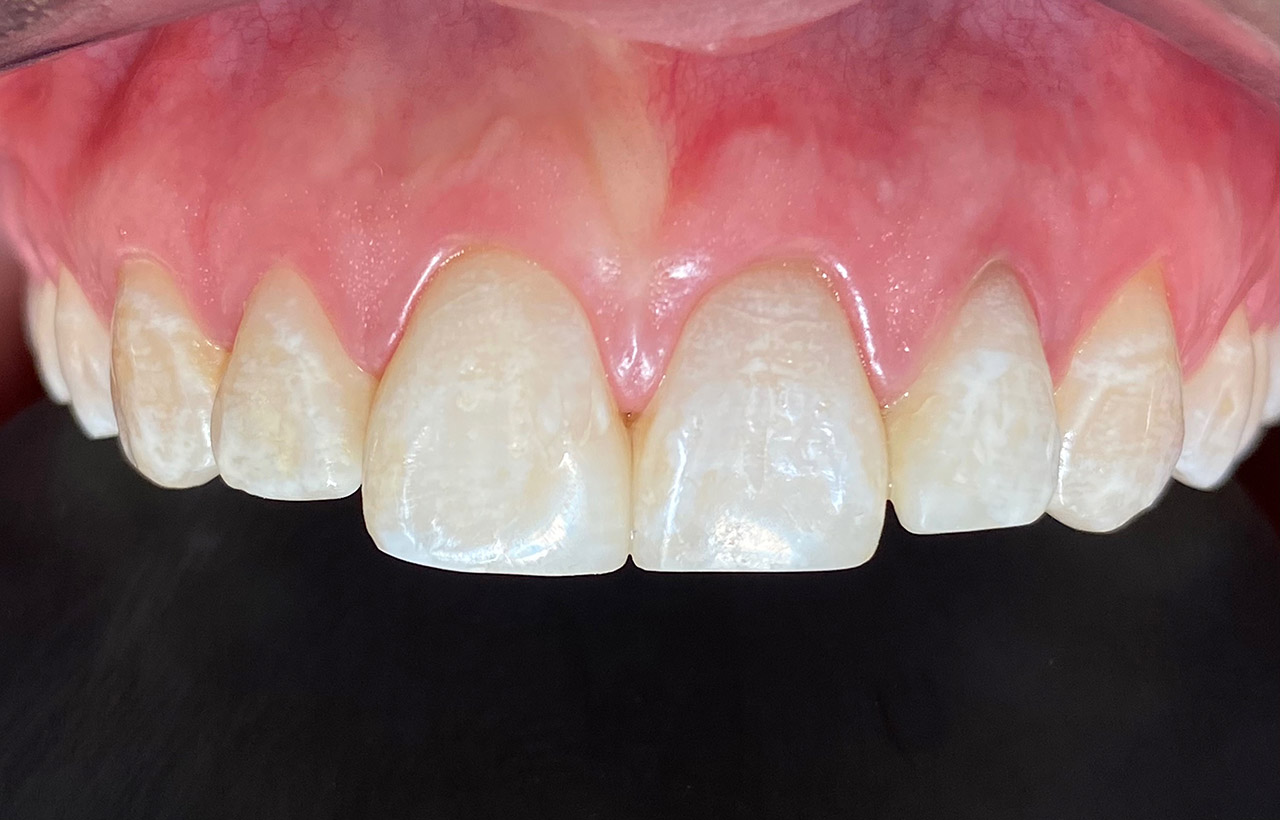

Traumatologie und Endodontie:

Nach Unfall/Sturz mittlerer Schneidezahn auf Gingivaniveau abgebrochen, Pulpa weit eröffnet, beide Nachbarzähne ebenfalls frakturiert.

Erstversorgung: Pulpektomie der Kronenpulpa, MTA, provisorischer Verschluß mit rosa Glasionomerfüllung.

Wiederaufbau der Nachbarzähne mit mitgebrachten (plus 1 Stein) Zahnstücken mit Kunststoff ergänzt und adhäsiv verklebt.

2. Schritt nach Aushärtung von MTA: Entfernung der Kronenpulpa im Bruchstück zur Vermeidung von Verfärbung, Füllung mit Kunststoff.

Adhäsives zementieren des abgebrochenen Zahnstücks.